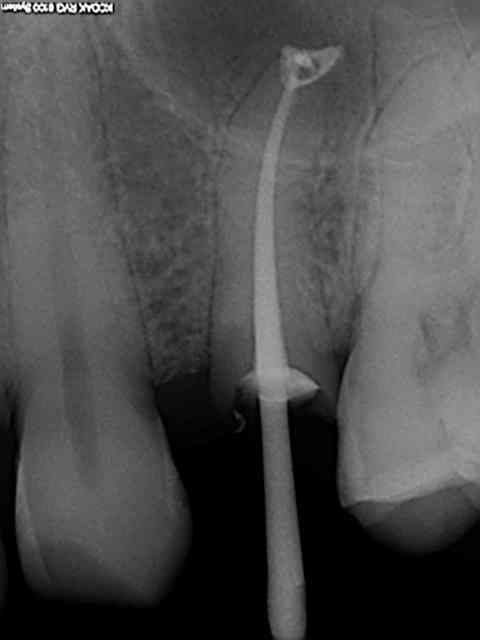

Ma radio est prise avant l'obturation!!

Ensuite je passe les cones fans l'hypochlorite puis je les seche et les enduits de ciments

J'envoi la photo post op la prochaine fois!, des que j'ai revu la patiente.